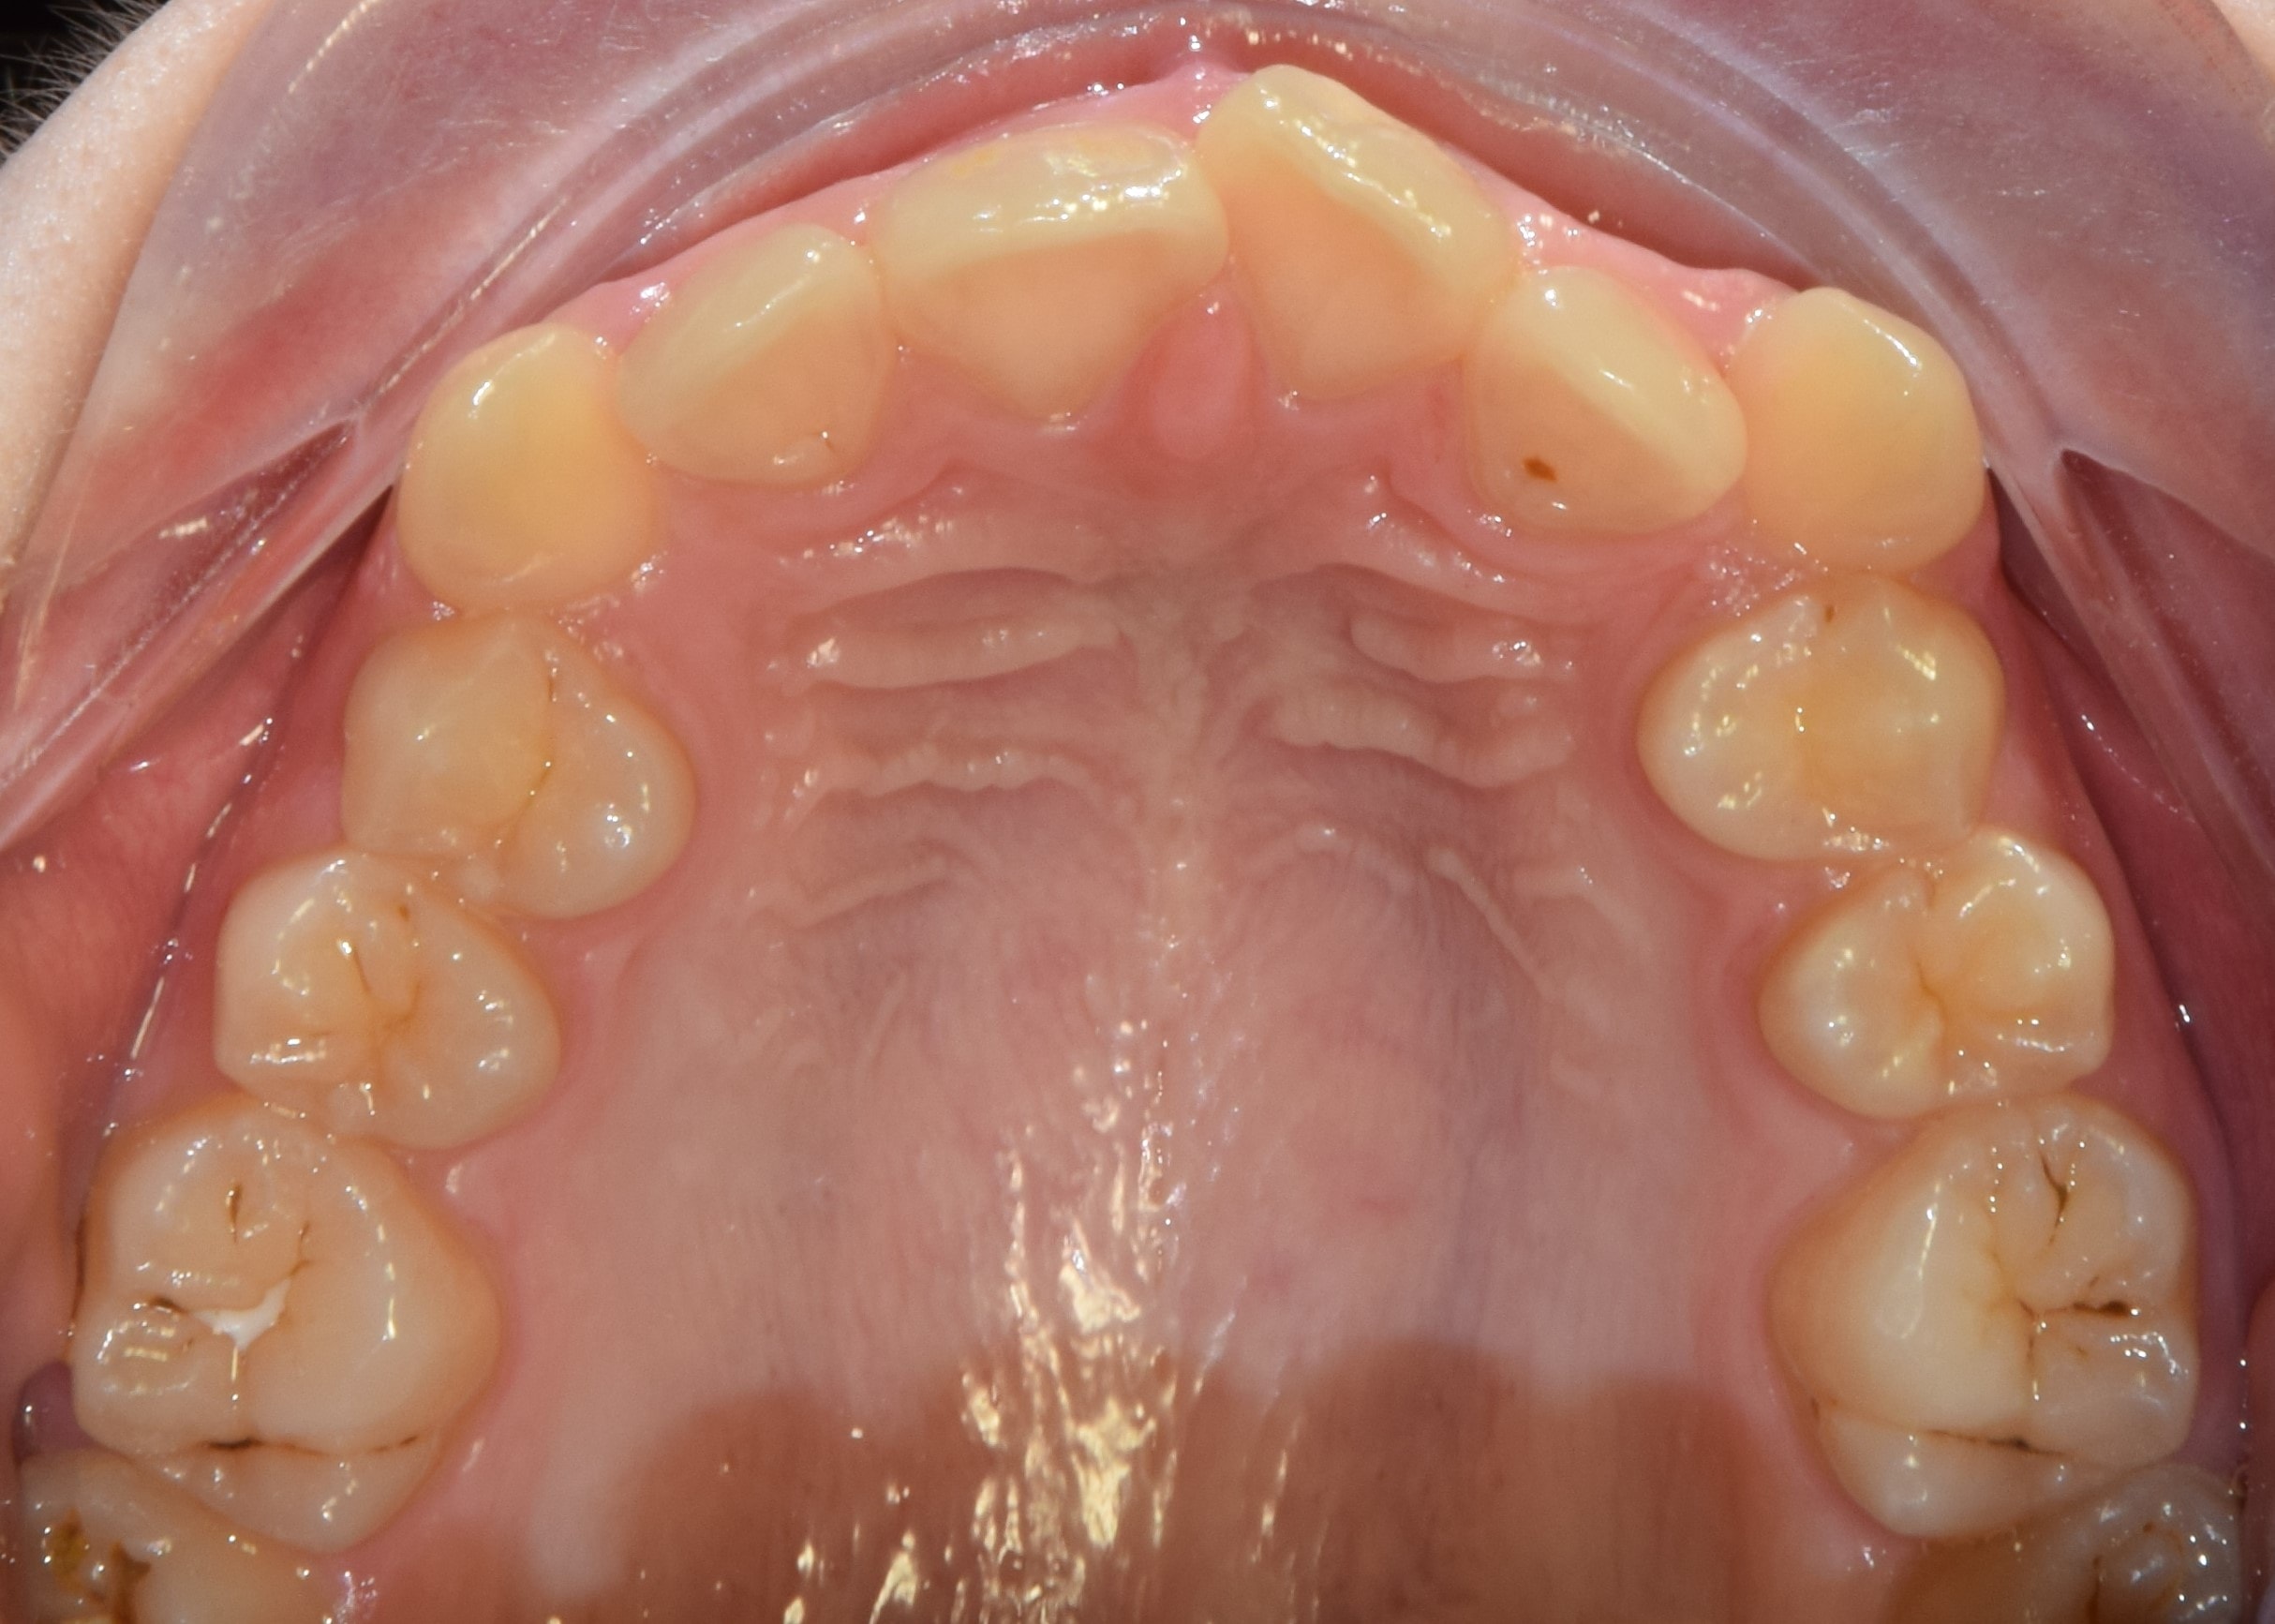

Fotódokumentáció

A fogszabályzó kezelés előtt-alatt-után rendszeresen készítünk fényképeket. Ez egy külön erre a célra összeállított tükörreflexes fényképezőgéppel történik. Nem a legkellemesebb élmény a fogszabályozás során, de utána nagyon jó lesz visszanézni a képeket. Sok fontos információt nyerhetek ki a készített fotókból, olyanokat is, amelyeket esetlegesen szájban nem veszek észre (nagyon kis méretűek), de egy nagy monitoron már könnyedén. A fotódokumentáció tehát még pontosabbá, precízebbé teszi a kezeléseim, és segít a maximum elérésében.